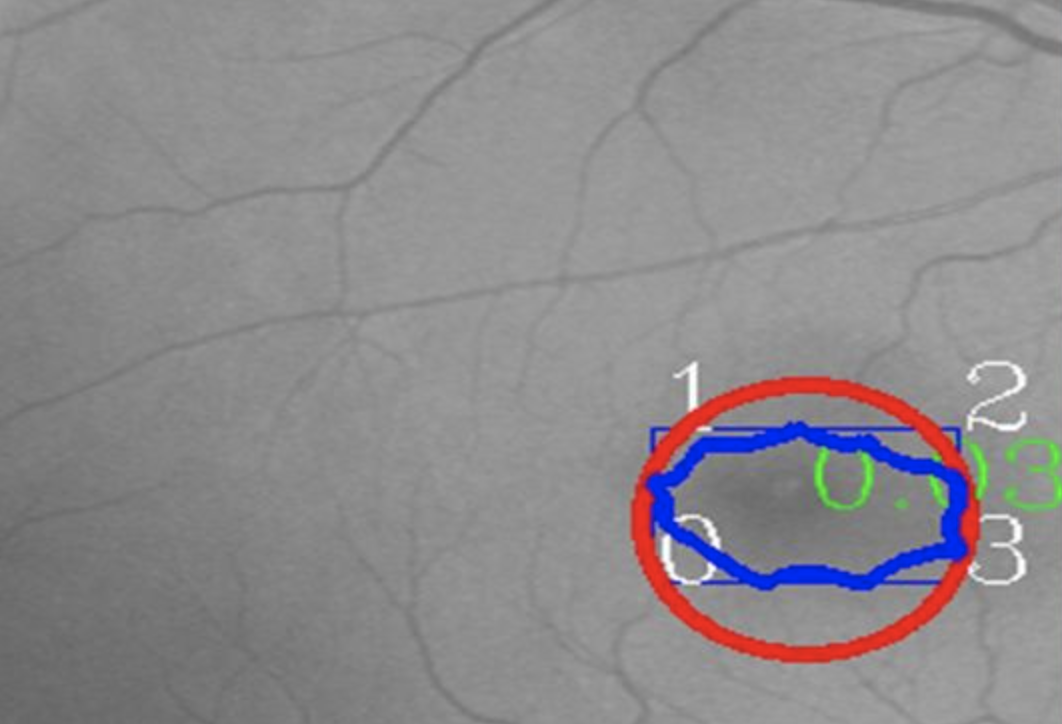

The performance of our model on Messidor-dataset:

When directly use unet model, we often get some error predictions. So I use a post-process algorithm: predicted area can't be to small. minimum bounding rectangle's height/width or width/height should be in 0.45~2.5 lefted area is the final output. The problem of this algorithm is that the parameters not self-adjusting, so you have to change them if input image is larger or smaller than before.